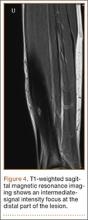

A 10-year-old boy was admitted for surgical repair of an inguinal hernia. Physical examination revealed a painless but tender anterior bowing of the right tibial diaphysis. The patient was a healthy-appearing white male with normal vital signs, gait, and posture. His parents noticed a slight protuberance of the tibia at age 2.5 years. No medical advice was asked for the bone swelling after that time. After recovery from the inguinal hernia repair 3 weeks later, the bone lesion was thoroughly examined. Radiographs showed an oblong, homogenous region of dense sclerosis in the diaphysis of the right tibia. The lesion had relatively well-defined margins and was located in the medullary cavity. Speculations were not obvious in the periphery of the lesion, which exhibited a sharp circumscription (Figures 1A, 1B). A well-defined lytic area was evident at the distal part of the lesion (Figure 1B). There was no periosteal reaction. Blood and serum chemistries were within normal limits, including serum calcium, phosphorus, and alkaline phosphatase. A conventional 3-phase bone scintigraphy (300 MBq) with technetium-99m HDP (hydroxydiphosphonate) indicated increased uptake in the area of the lesion but no other skeletal abnormality (Figure 2). Computed tomography (CT) showed that the lesion was purely intramedullary and densely blastic. The lesion originated from the medial cortex, which was thickened (Figure 3A). The lesion extended to the anterolateral cortex, which was thinned and included a lytic area. In the distal part of the lesion, the anterolateral cortex was thickened, included lytic areas, and exhibited an anterior portion of cortical destruction (Figure 3B). The fatty marrow adjacent to the region of sclerosis appeared normal. There was no evidence of extraosseous soft-tissue changes. On both T1- and T2-weighted magnetic resonance imaging (MRI), the lesion exhibited low-signal intensity. The lesion measured 10.8×2.2×1 cm. It originated from the medial cortical bone of the tibia, blended into the medullary cavity, and extended anteriorly towards and through the anterior cortex. The area of cortical destruction was clearly evident on the axial MRI. The periosteum was displaced and eroded anteriorly by focal radiating bony streaks. No enhancement was seen after the intravenous administration of gadolinium-diethylenetriamine pentaacetic acid (Gd-DTPA) as a contrast medium. There were no extraosseous soft-tissue changes. In the distal part of the lesion, sagittal and axial MRI showed a 1.2×0.8×0.7-cm well-defined ovoid focus, with characteristics of cystic degeneration that exhibited intermediate-signal intensity on T1-weighted MRI (Figure 4) and high-signal intensity on T2-weighted MRI.